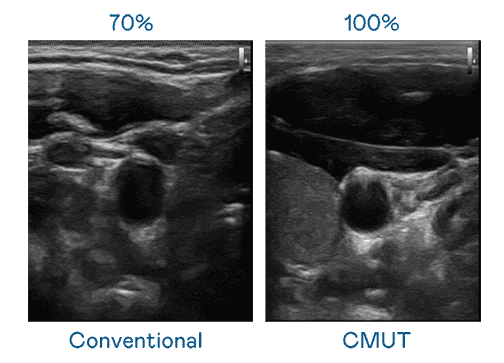

CMUT 技术是一种用电容式微机电元件来产生超音波讯号的技术。。。。与传统 PZT 压电式技术相比,,,,CMUT 频宽增加 30%,,,更宽频的超音波讯号让影像解析度大幅提升,,,,是实现高影像品质医疗超音波扫描、、促进精准医疗发展的关键技术。。

大频宽带来超清晰影像

超音波影像的解析度高低,,,首先取决于探头能发出的讯号频宽。。欧陆注册 CMUT 可提供高清晰的超音波讯号,,,,提供高频宽、、、高灵敏度、、影像纹理细节更高的超音波影像,,,协助医护人员缩短影像判读时间及利用精准的医疗影像进行诊断。。。。